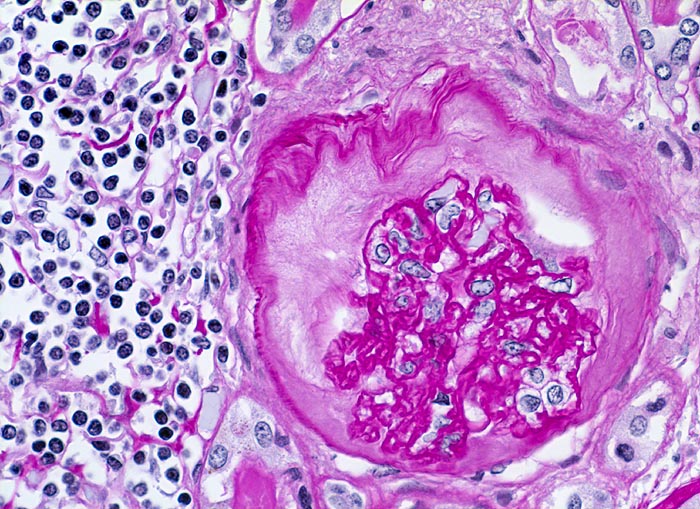

Histologisch finden sich neben völlig unverändertem Parenchym herdförmige Infiltrate aus Lymphozyten, Plasmazellen, Histiozyten und bei akutem Schub zusätzlich neutrophile Granulozyten. Das destruierte Gewebe wird durch Granulationsgewebe im Intersititum organisiert. Gruppen erhaltener Tubuli mit vergrössertem Durchmesser und abgeflachtem Epithel gefüllt mit Harnmukoid (=Tamm-Horsfall Protein und/oder IgA) bilden Pseudostrumaherde ( 1793). Diese sind ein wichtiger Hinweis aber kein Beweis für chronische Pyelonephritis. Bei Kindern finden sich oft zusätzlich Lymphfollikel. Glomeruli kollabieren und zeigen eine konzentrische periglomeruläre Fibrose. Oft findet sich eine Arteriolosklerose und eine adaptative Intimafibrose grösserer Arterien. Obligat findet sich eine schwere chronische Pyelitis sowie eine Fibrose von Nierenbecken und Nierenmark. Bei fortgeschrittener bilateraler Nierenschädigung kommt es zum Auftreten einer Überlastungsglomerulopathie, die meist unter dem Bild einer segmentalen fokalen Glomerulosklerose in Erscheinung tritt.